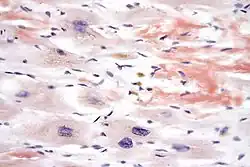

Micrograph demonstrating amyloid deposition (red-orange) with Congo red staining in cardiac amyloidosis

In histology and microscopy, Congo red is used for staining in amyloidosis, and for the cell walls of plants and fungi, and for the outer membrane of Gram-negative bacteria. Apple-green birefringence of Congo red stained preparations under polarized light is indicative of the presence of amyloid fibrils. Additionally, Congo red is used for the diagnostics of the Shigella flexneri serotype 2a, where the dye binds the bacterium's unique lipopolysaccharide structure. Furthermore, Congo red may also be used to induce expression of the type III secretion system of Shigella flexneri, bringing about the secretion of IpaB and IpaC, which form translocation pores within host cell membrane, allowing effector proteins to pass through and alter the host cell's biochemistry. The dye can also be used in flow cytometry experiments for the detection of Acanthamoeba, Naegleria and other amoebal cysts. In confocal microscopy, Congo red can be used as a stable fluorescent stain.[5]